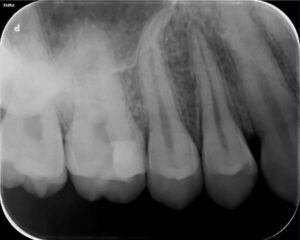

治療前

右上の奥歯の痛みが主訴でご来院されました。

右上6番に大きな虫歯があり、虫歯の範囲が歯の中の神経に近接していました。通常の保険診療では歯の神経を抜く治療(歯の根の治療)になりますが、電気的な検査で神経の反応は正常であったので、虫歯治療と神経の保存療法(歯髄保存療法)を提案し、患者様の合意を頂いたので治療をすすめることになりました。

上のレントゲン写真では右上6番に虫歯で歯が溶けている部分があります(矢印部) 。